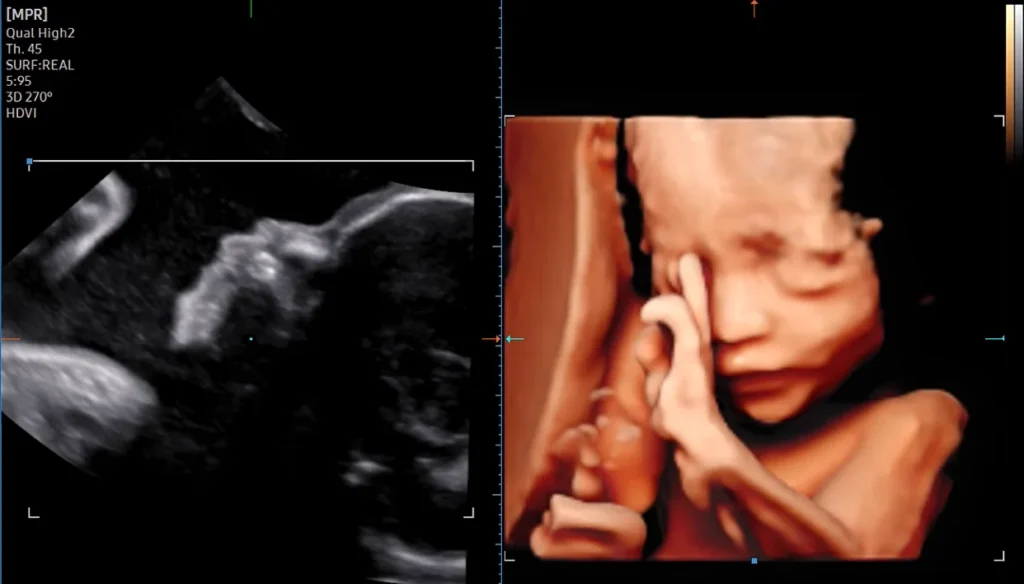

3D/4D Fetal / Obstetric Ultrasound

High-definition 3D Fetal images for better anatomical assessment and parental bonding.